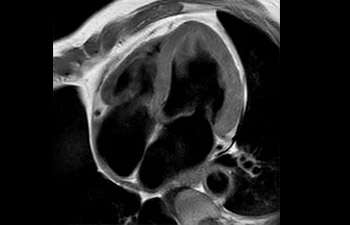

con Compressed SENSE